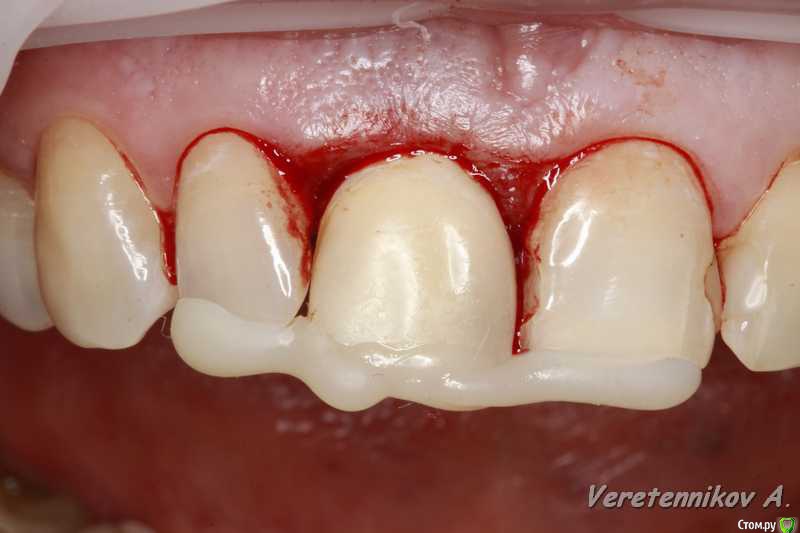

Популярный пост an_ver Опубликовано 15 января, 2016 Популярный пост Поделиться Опубликовано 15 января, 2016 11,жил долго и счастливо..но тут Новый год(((, скол ниже уровня ЦЭС на 3 мм...от экструзии отказалась.Из своего зуба сколхозил шаблон,чтоб наверняка. Удалил,кюретаж,вестибулярка целая, SPI 4.2*13 мм,с бугра ССТ,на всякий)),в щели Апатос,врем.абатмент,врем.коронка из своего зуба. 1ч.20мин.)) 27 Ссылка на комментарий

k.t.m. Опубликовано 15 января, 2016 Поделиться Опубликовано 15 января, 2016 в щели апатос,сст в сформированный карман! Андрей красиво и все по пунктам,как так вышло что сосочек порвался?может не стоило так глубоко сст заводить? 1 Ссылка на комментарий

an_ver Опубликовано 16 января, 2016 Автор Поделиться Опубликовано 16 января, 2016 (изменено) в щели апатос,сст в сформированный карман! Андрей красиво и все по пунктам,как так вышло что сосочек порвался?может не стоило так глубоко сст заводить?Чесно,фиг знает((( тока счас обратил внимание,наверно 15С орудовал глубоко (набор Деплер для туннеля в клаве был),((( немного лоскут перфорнул...если кто заметил,решил глубже завести ластик сст Изменено 16 января, 2016 пользователем an_ver Ссылка на комментарий

an_ver Опубликовано 16 января, 2016 Автор Поделиться Опубликовано 16 января, 2016 Клёво!!!Можно вопрос: как сст всовывали ?Просто опыта в этом аспекте очень мало и понятие "в щели" не совсем понятно.СпасибоВ щели: это свободные обьем лунки,после установки импланта,т.е. все пустоту забиваем графтом (Апатос). По ССТ: скальпель 15С, параллельно кости осторожно,маятниковыми движениями,до уровня прикрепления или глубже формируете карман,вкол с вестибулярки-выкол в лунке,вкол в сст,выкол там же,далее вкол внутри кармана и затягиваете сст...но проще посмотреть...сейчас А.Смолякова по рецессии выложила видео,принцип такой же 2 Ссылка на комментарий